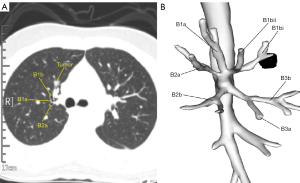

The lesion was close to the segmental hilum; however, CT and bronchopulmonary vascular 3-dimensional (3D) reconstruction suggested that a planned resection of S3b + S1bi would ensure adequate margins (Figures 1,2). The selected surgical approach used a 3.5-cm single-port incision between the midaxillary line and the posterior axillary line in the right 4th intercostal space. The surgery lasted approximately 200 min, with an intraoperative blood loss of approximately 40 mL. Frozen sections indicated in-situ adenocarcinoma, which was confirmed in the paraffin sections. The thoracic drainage tube was withdrawn 4 days after surgery. The patient was discharged on the 5th postoperative day without complications or adverse events, except slight chest pain that lasted for about 2 weeks postoperatively. Chest CT scans in the 12th and 24th months after surgery showed good lung recovery, and no atelectasis or pulmonary congestion was observed. The treatment timeline of the current case is showed in Figure 3 and the 3D reconstruction was performed using Vitaworks (www.vitaworks.cn).

Preoperative planning

According to the CT findings and the results of the preoperative 3D reconstruction (see Figure 2), the branching pattern of the bronchi was the “defective B2” type (B1 + B2a, B3 + B2b). The nodule was adjacent to B1bi and close to the b subsegment of the anterior segment (S3b). Thus, a resection of S3b + S1bi was planned. CT revealed that the lesion was approximately 2 cm from the beginning of B1bii; thus, the B1bii had to be exposed intraoperatively to ensure an adequate margin in this direction (see Figure 2).